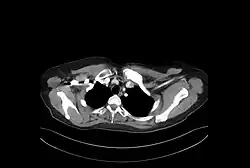

Síndrome SAPHO

Esta síndrome possui etiologia desconhecida. É caracterizada por:

- 4)Hiperostose - Espessamento irregular do tecido ósseo subperiosteal

- 5)Osteíte inflamatória